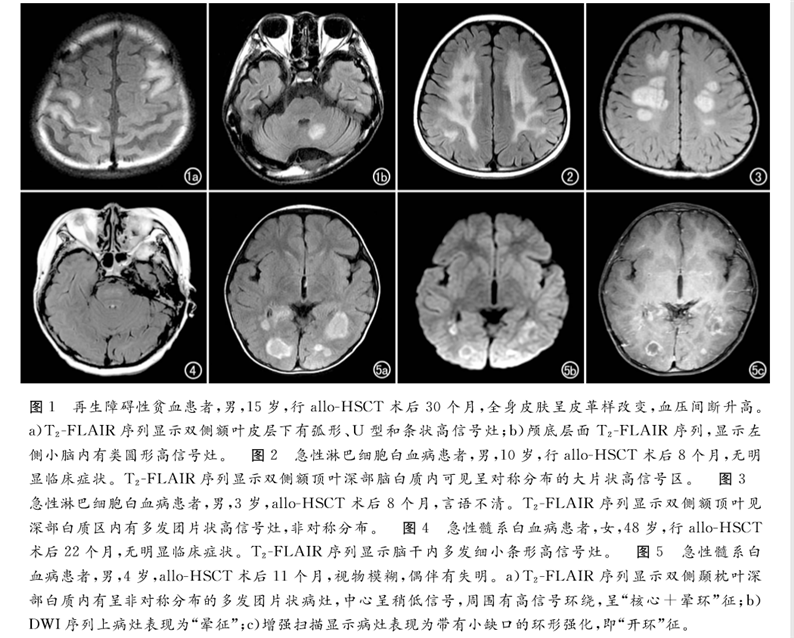

論文回顧性分析了2013年6月—2017年12月北京陸道培醫(yī)院確診為allo-HSCT后并發(fā)中樞神經系統(tǒng)慢性移植物抗宿主病的12例血液病患者的臨床和影像學資料。得出結論,MRI是發(fā)現(xiàn)血液病異基因造血干細胞移植(allo-HSCT)后并發(fā)中樞神經系統(tǒng)慢性移植物抗宿主病的有效手段,可以提高對本病的診斷及鑒別水平,為臨床制訂佳治療方案提供幫助。